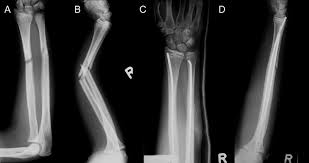

Bei den dabei verwendeten sogenannten Marknägeln handelt es sich meist um Implantate aus Titan oder Edelstahl. Die Diagnose Multiples Myelom in Deutschland fälschlicherweise oft mit dem solitären Plasmozytom gleichgesetzt löst Schock Angst und Ratlosigkeit aus. Es blieben subtrochantär große Löcher im Femur mit einer lateralen kortikalen Lücke von 12x12 mm und einer weiteren.

Immerhin wird das Bein bin zum Knochen geöffnet Gewebe und Muskeln durchtrennt und es verbleiben Löcher in den Knochen. Die Schraube im Schenkelhals ließ sich noch lösen die zwei Verriegelungsschrauben jedoch nicht - die Schraubenköpfe brachen ab die Gewinde wurden überbohrt und brachen wieder ab. Da die Drähte bei auch nur leichter Lockerung eine Gefahr für Strecksehen darstellen gibt es sehr gute Gründe die Kirschnerdrähte zu entfernen.

Es wurde schließlich alles Metall entfernt aber leider zu einem hohen Preis.

Gelegentlich ist es nicht möglich das Material vollständig zu entfernen so dass es auch vorkommen kann dass Reste des Metalls im Körper belassen werden müssen. Ich habe neulich das Gleiche bei einem Schrank erlebt. Die Stabilität sollte nach der Entfernung kein Problem sein weil die Schrauben und Nägel immer versetzt angeordet sind also die Löcher nie über- untereinander lägen. Die ist hart und sehr spitz und lässt sich nicht bewegen. Sollten Metallteile weggebrochen sein werden die dann auch im Knochen belassen die tun nix. Hier ist die Radiusfraktur nicht mit einer Platte sondern mit Kirschnerdrähten erfolgt. Obwohl ein Schraubenloch noch lange im Röntgenbild nachweisbar ist kommt es zu einer fortschreitenden Geflechtknochenbildung die die Stresskonzentration im Schraubenloch zunehmend herabsetzt. Hierbei wird in manchen Fällen lediglich die einzelne Stellschraube entfernt wobei die komplette Metallentfernung ungefähr nach einem Jahr beginnt. Auch nach einem Jahr kann man im Röntgenbild nach einer Schraubenentfernung die Schraubenkanäle gut erkennen.